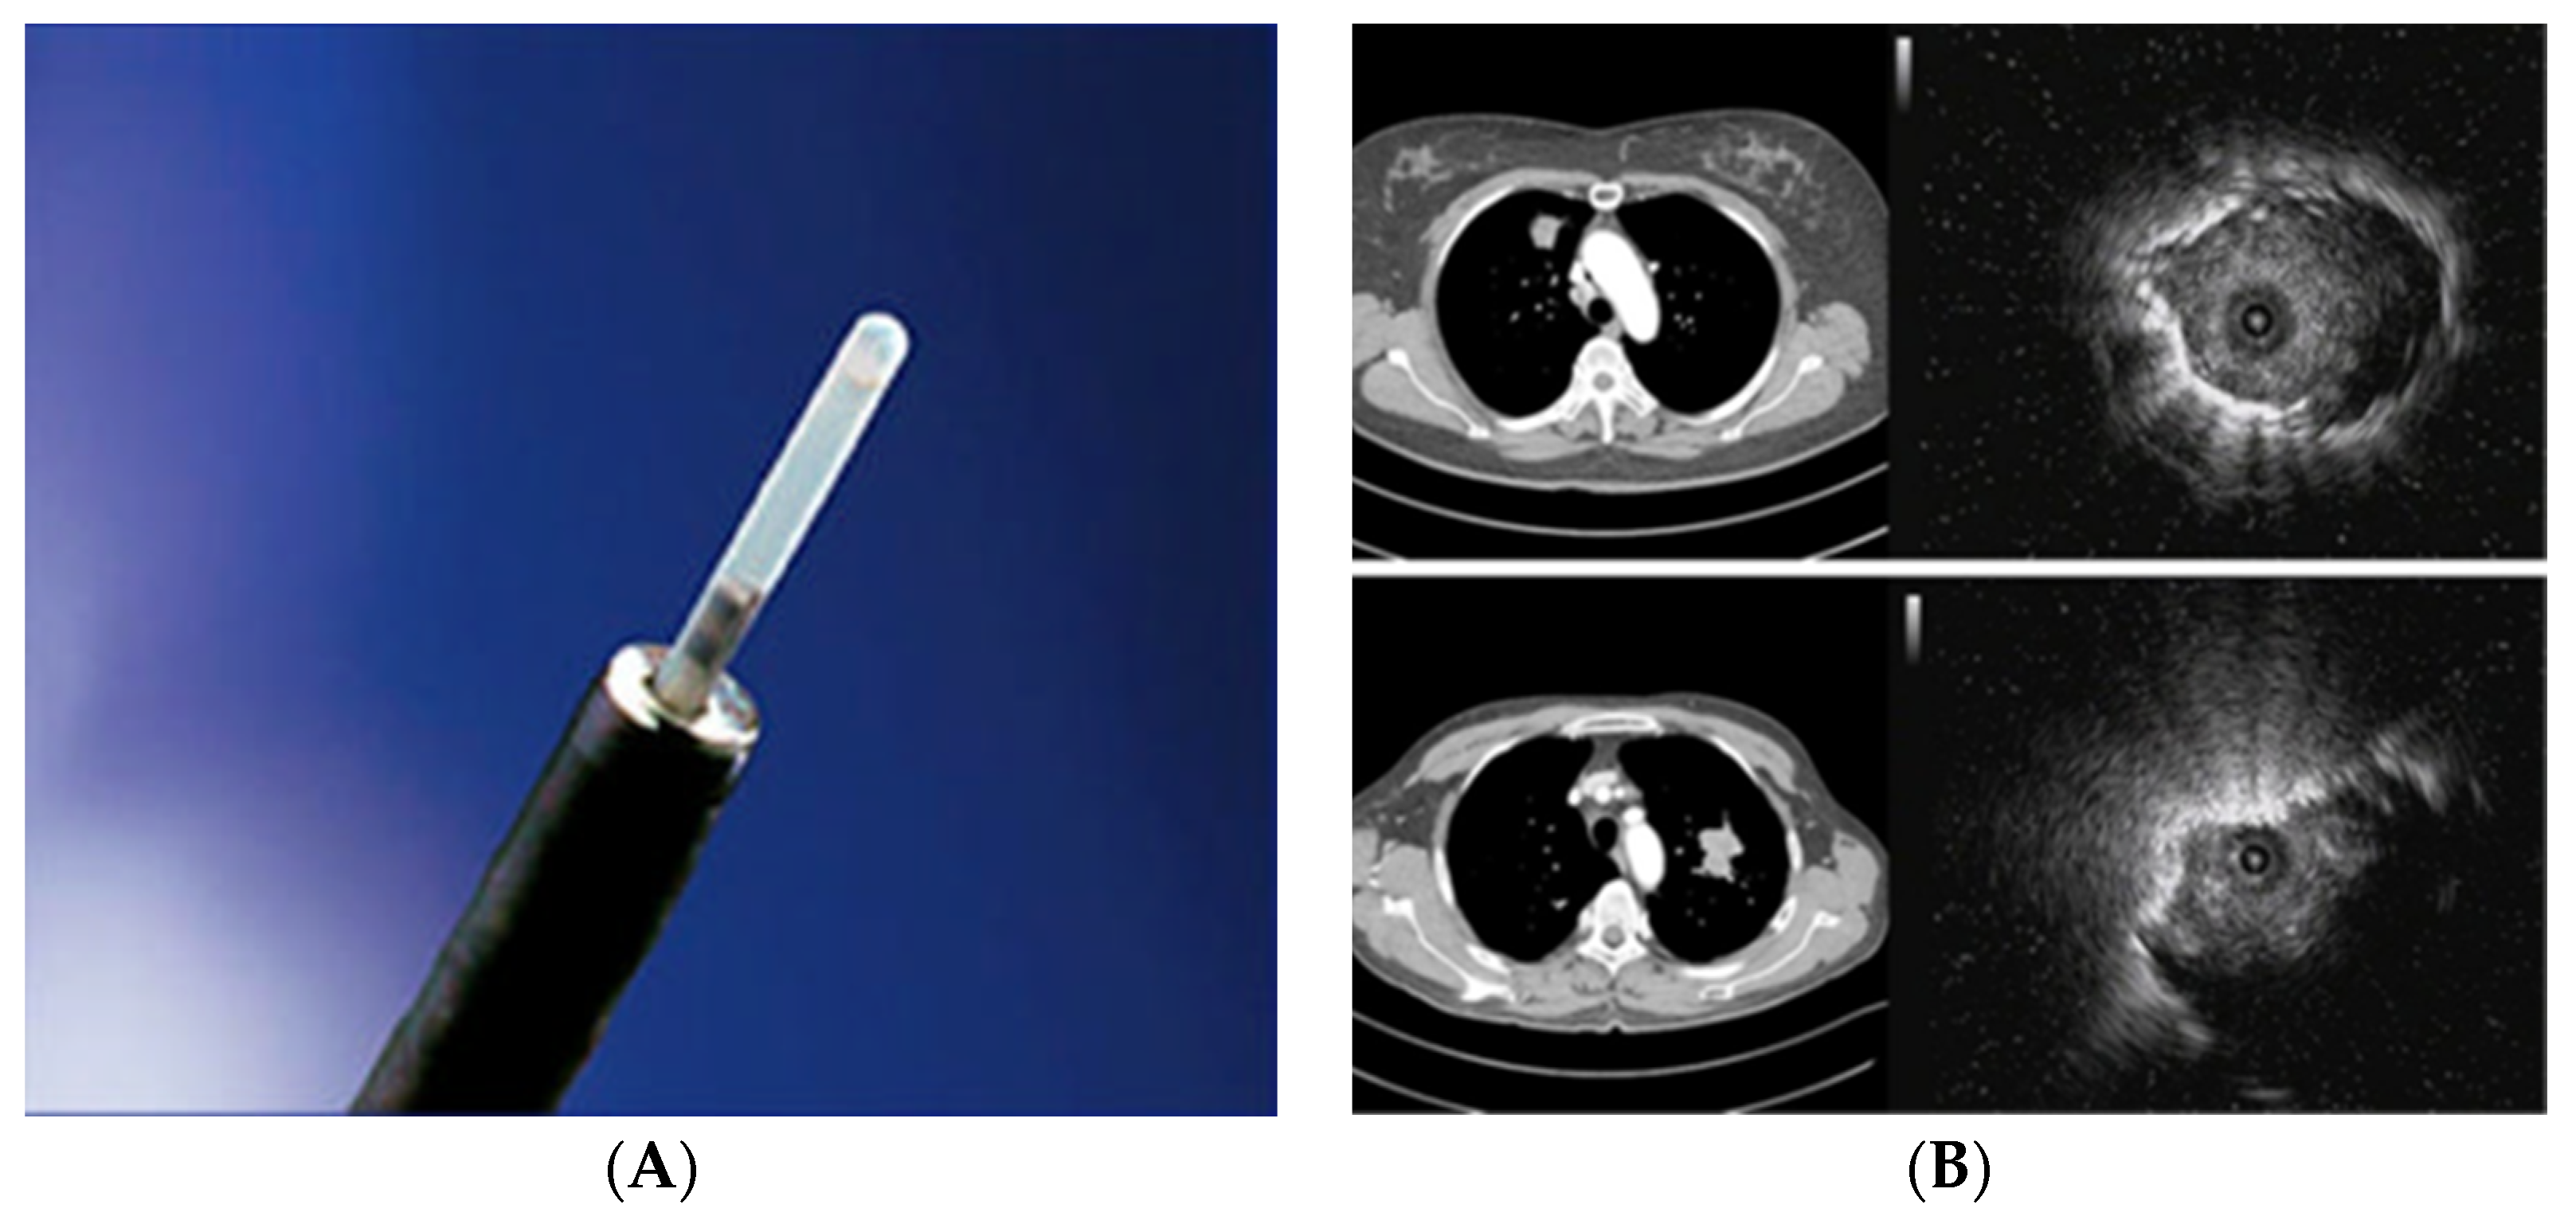

2.2. Radial Probe—Endobronchial Ultrasound with a Guide Sheath in the Diagnosis of Peripheral Lung Lesions

RP-EBUS-GS—Guided Endobronchial Ultrasound in the Era of Molecular Testing of Tumor Tissue

2.3. Endobronchial Ultrasound (EBUS) Transbronchial Needle Aspiration